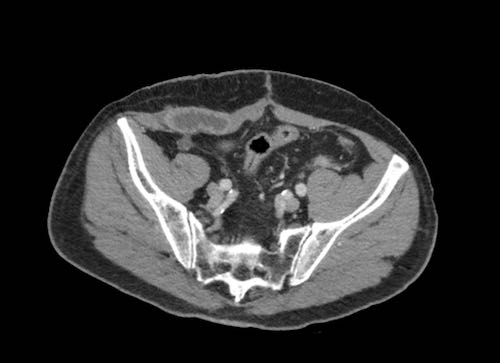

Cuộn xem ảnh CT

Ca lâm sàng 1

Cuộn qua các lát cắt.

Bạn có thể phát hiện tất cả các tổn thương cấy ghép phúc mạc không?

Bệnh nhân này đã được phẫu thuật và toàn bộ phúc mạc được ghi nhận phủ kín bởi các tổn thương u dạng kê.